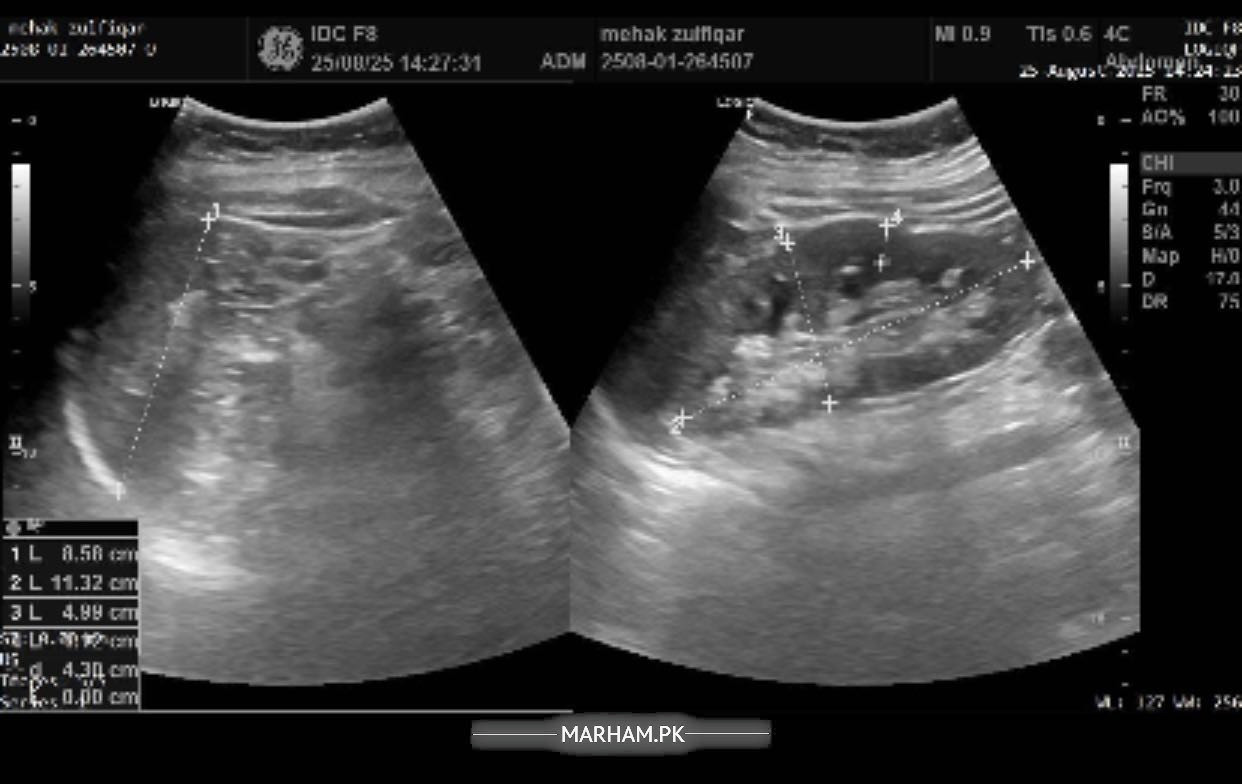

Pain in the right side of abdomen under the ribs followed by backache in the same area. In addition to these symptoms having difficulty concentrating, having confusion, difficulty speaking facial muscles hurt, sleepiness all the time, fluctuations in bp and feel nauseous with sometimes developed fever or shivering. Please help me with this. Will be highly thankful. Attached my reports too.

Sr this is the most recent ultrasound report. But radiology isn’t matching my blood reports. I am worried about that. Pls help.

Sr can’t share pics altogether but here it is

Another

report of ultrasound

you’re demonstrating features of UTI, blood in urine can be due to many things, would like to explore this in detail and get to do few more tests. I’m available for consultation

Okay I think you need proper consultation, and a proper ultrasound from a consultant. I’m available or if you want to see anybody of your liking you should. in the meantime i need you to make a record of your bp for a week, 2 readings in the morning and 2 readings at night then tell me